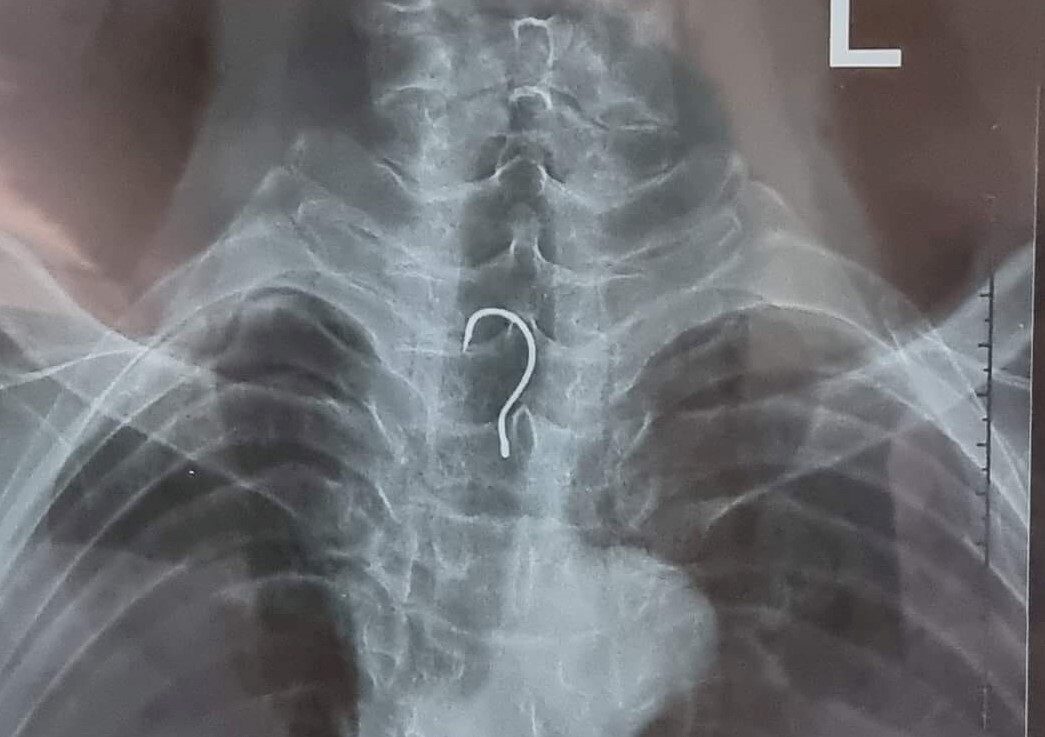

Lưỡi câu mắc trong thực quản. (Ảnh: BV cung cấp)

Ông A. được người thân đưa vào Bệnh viện Đa khoa tỉnh Hà Tĩnh thăm khám sau nhiều ngày ăn uống khó khăn. Các bác sĩ phát hiện một chiếc lưỡi câu có chiều dài gần 4cm, vòng cung rộng gần 1,5cm, nằm trong thực quản của bệnh nhân.